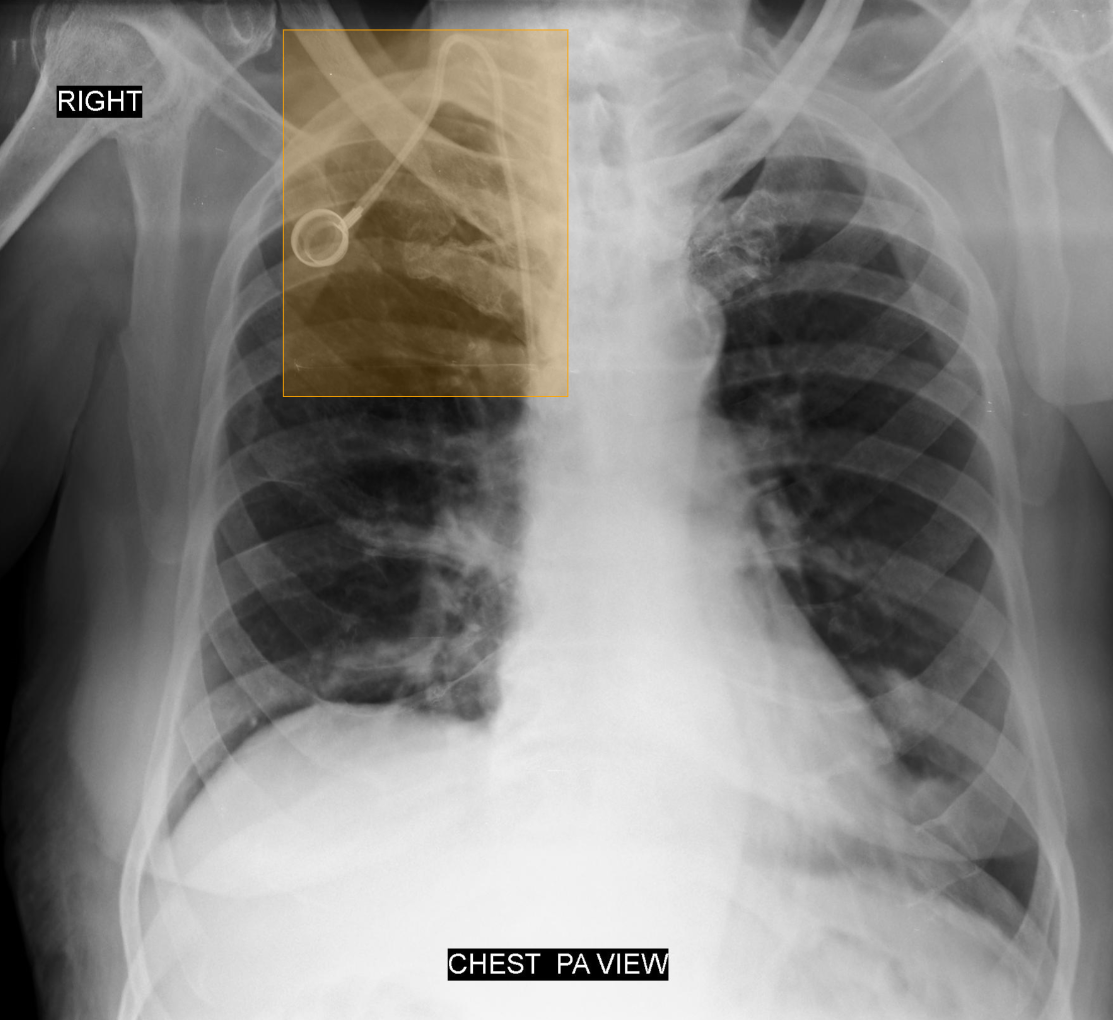

What does AI-detected pathology look like?

Eight examples of AI-annotated chest X-rays with color-coded pathology overlays

Chest X-ray with AI-detected Foreign Body (Chemoport) highlighted

Foreign Body (Chemoport)